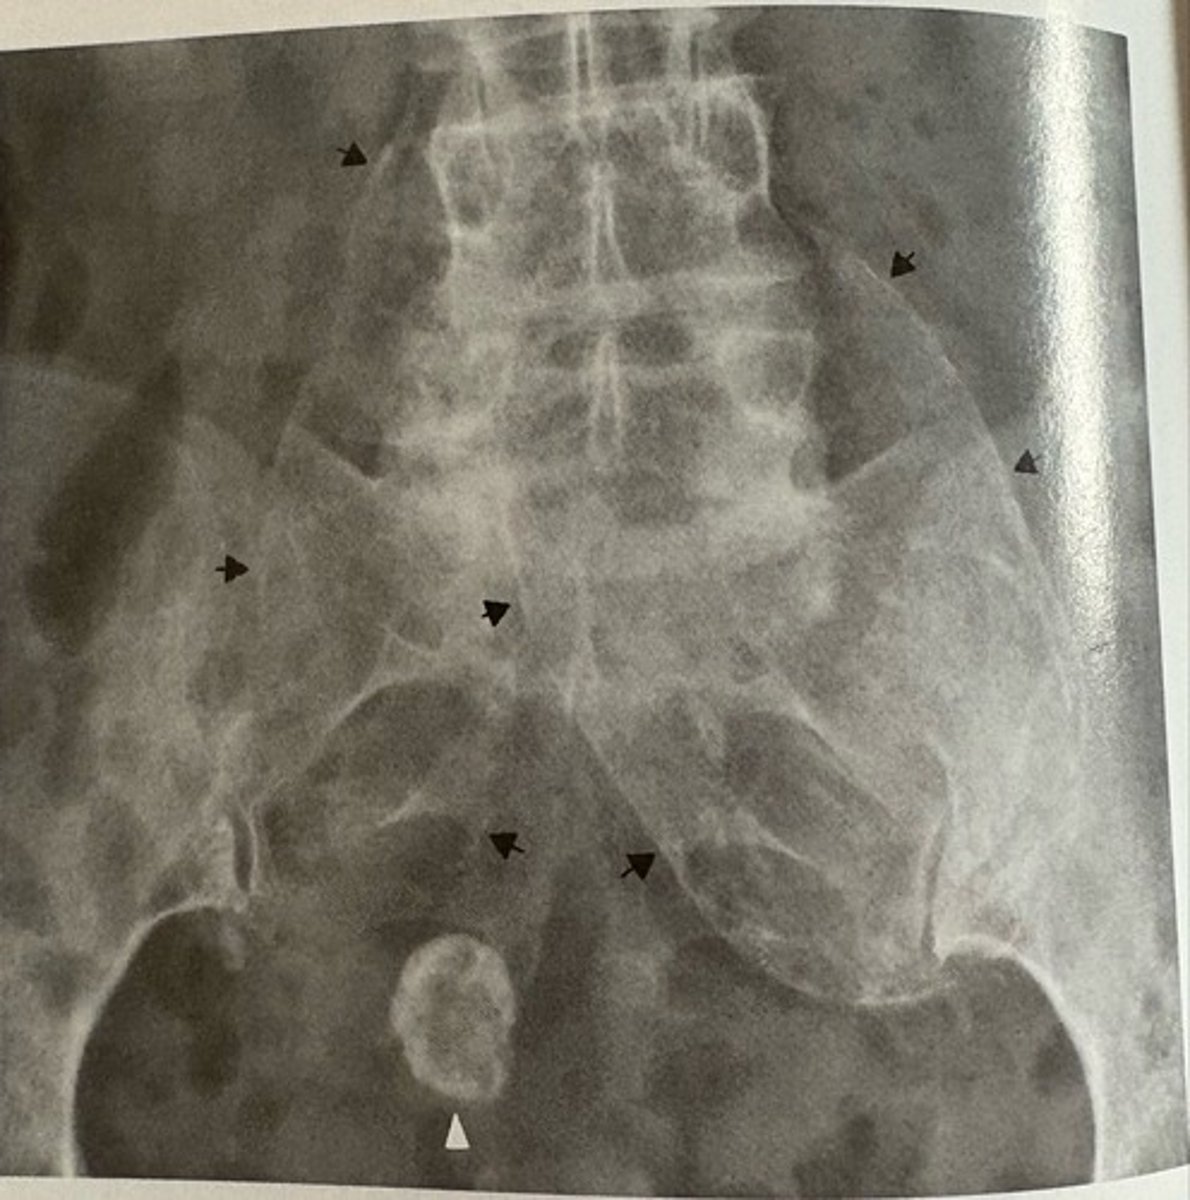

abdominal aorta aneurysm

what pathology is present?